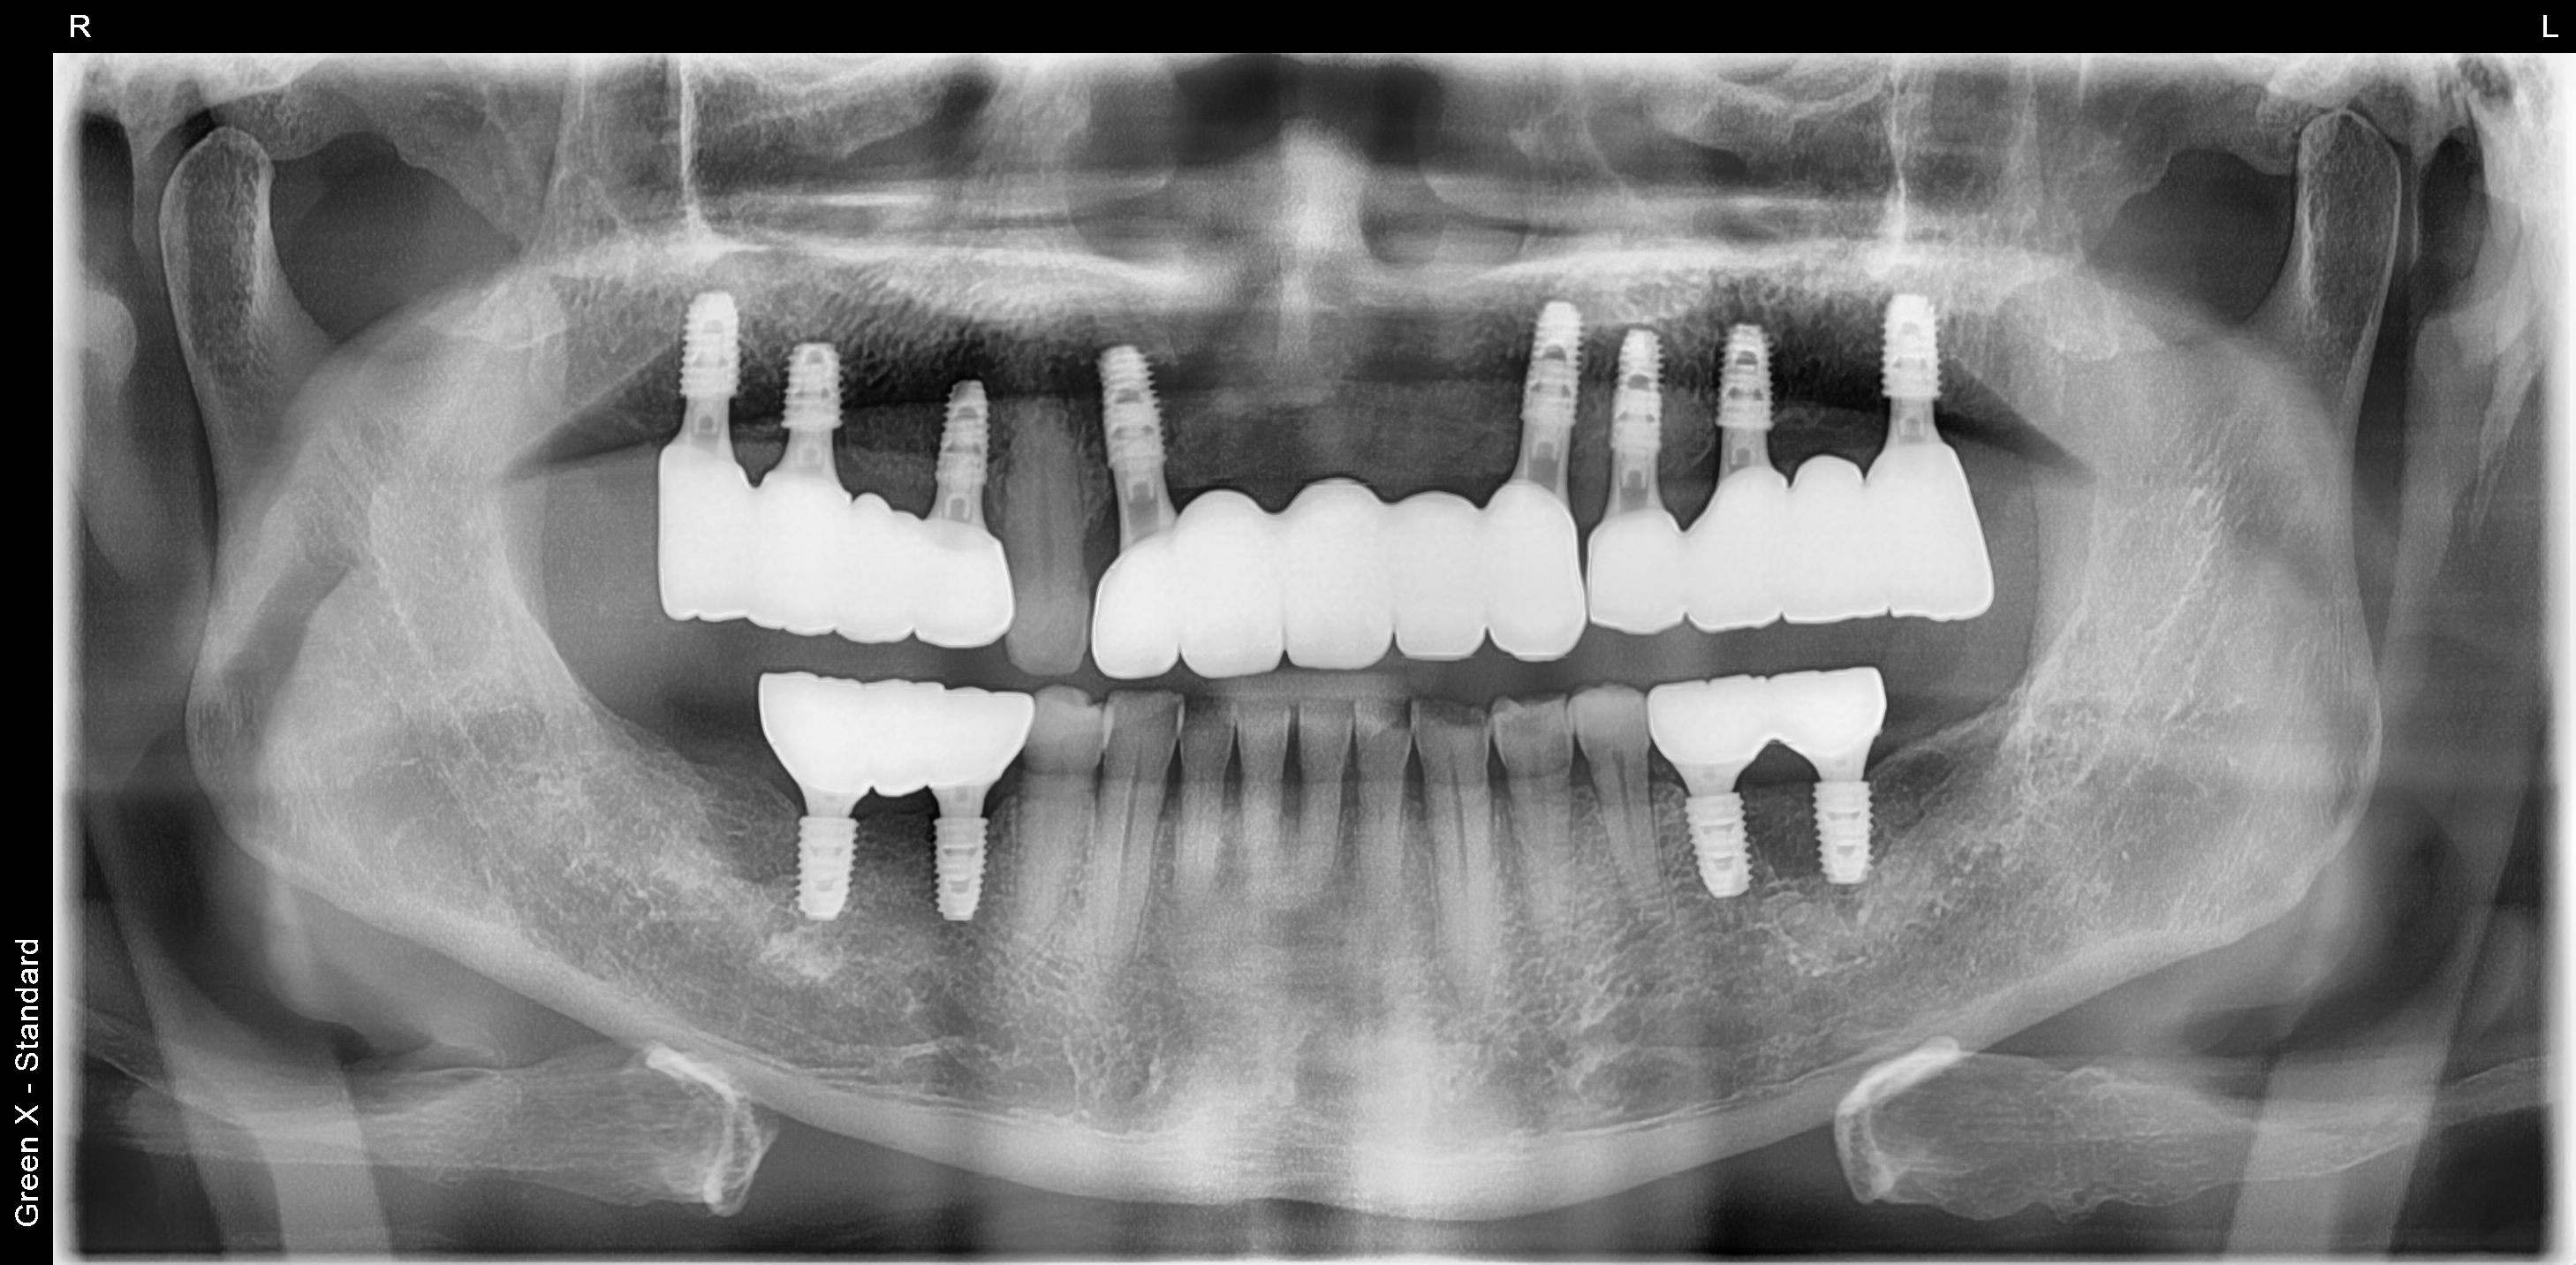

위턱에는 8개의 임플란트를 식립하여 전체 치아를 수복해드렸고,

아래턱은 4개의 임플란트를 식립하여 어금니를 수복해 드렸습니다.

<치료 후>